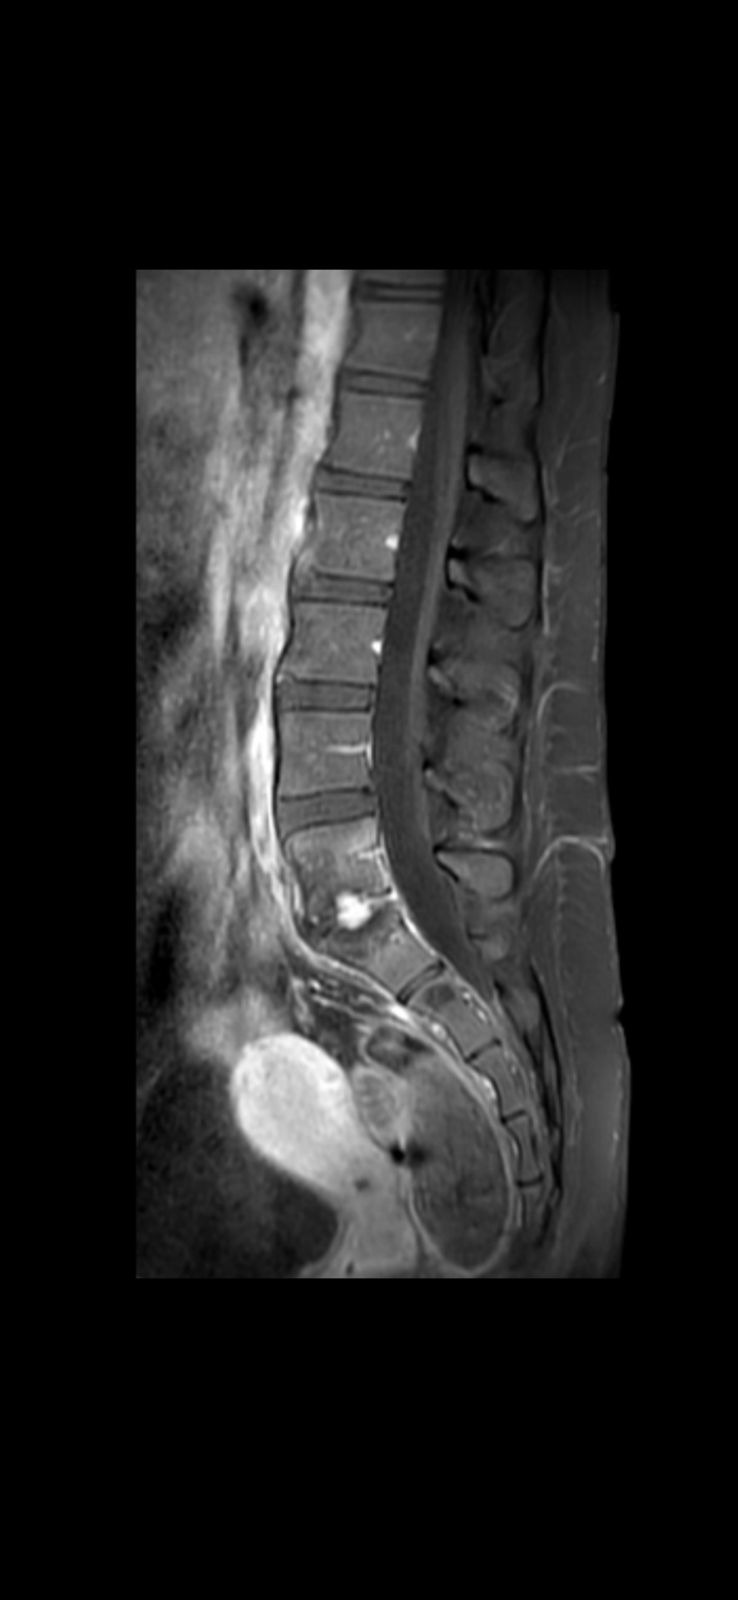

Tengo una infección en la columna, específicamente en L5-S1, que está destruyendo mi hueso. Los médicos necesitan operarme para lijar el hueso infectado y detener el daño. Si no me operan cuanto antes, esto puede empeorar y dejarme con secuelas permanentes.